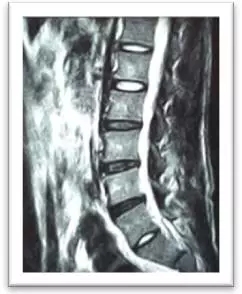

(術(shù)前)

劉志安副院長經(jīng)查看MRI(核磁共振成像)結(jié)果后,顯示小姚腰5/骶1椎間盤突出,髓核左下方游離,情況已經(jīng)比較嚴重,遂收住入院。